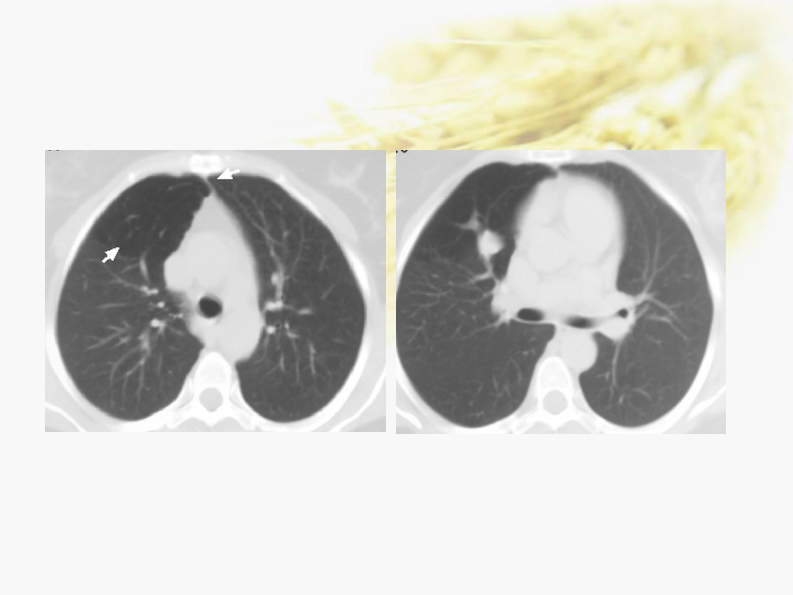

肺部先天性疾病-陈宏伟.pdf